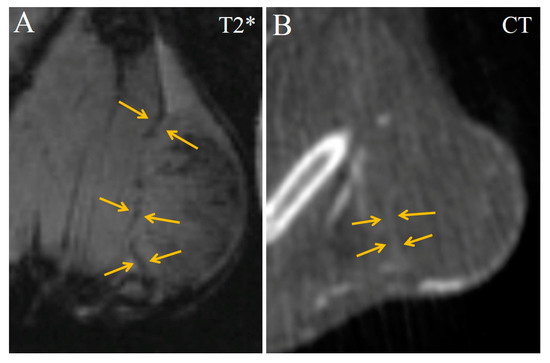

2. Results